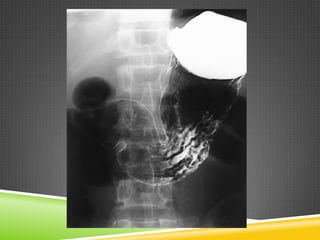

BARITADOS.

 Sal metálica.

 No se absorbe por vía gastrointestinal.

 No produce artefactos.

 Eliminación en las heces fecales.

 Grado de excreción en función del tránsito GI.

 Tiende a sedimentarse.

CONTRAINDICACIONE

S.

Obstrucción próxima del cólon.

Presencia o sospecha de perforación GI

o fístula traqueesofagica.

BARITADOS.  Sal metálica. No se absorbe por vía gastrointestinal.  No produce artefactos.  Eliminación en las heces fecales.  Grado de excreción en función del tránsito GI.  Tiende a sedimentarse.

CONTRAINDICACIONE S. Obstrucción próxima delcólon. Presencia o sospecha de perforación GI o fístula traqueesofagica.